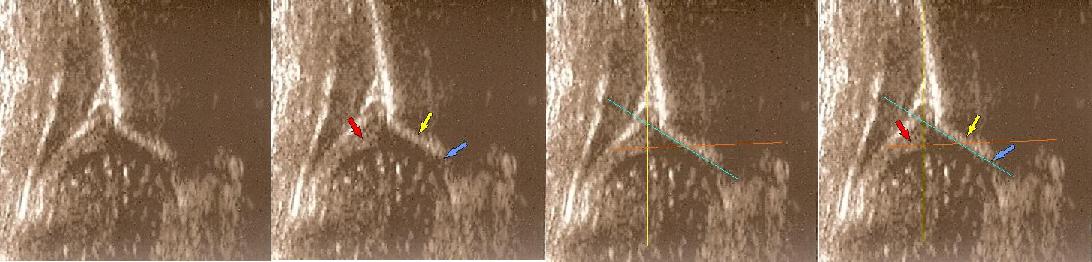

W przypadku mniejszych wartości dla Kąta a 43-49 stopni i wartości poniżej 77 stopni dla kąta B, oceniamy biodro jako typ lIc (biodro "krytyczne","zagrożone").Jeżeli w badaniu klinicznym znajdujemy cechy niestabilności z z objawem Ortolaniego to takie biodro określamy jako IIc niestabilne .Kiedy głowa przemieszcza się dalej a kąt B przekracza wartość graniczną decentracji powyżej 77 stopni to takie biodro zaliczamy do typu D.

Typ IIc dach chrzestny jeszcze pokrywa

Typ IIc kropki pokazują od lewej obrąbek, spłaszczony występ kostny 2 punkty ,gałąź dolna

Typ IIC prawidłowo wykreślony

poniżej 4tyg.ż. dach kostny bardzo niewystarczajacy;brzeg kostny spłaszczony

;dach chrzestny jeszcze pokrywa ( obraz przypomina odwrócone V)

dolne zdjęcia

strzałki pokazują obrabek(czerwona):brzeg kostny (żółta);gałąż dolna(niebieska) ,

prawidłowy przebieg linii dachu kostnego(niebieska) stycznie do echa gałęzie dolnej i echa brzegu kostnego ;

linii dachu chrzęstnego (czerwona) stycznie do brzegu kostnego i przez środek geometryczny obrąbka i

linii podstawnej ( żółta równolegle do sylwetki kości biodrowej po zewnetrznej stronie prze punkt gdzie ochrzęstne przechodzi w okostna i styka sie z echem kości

Typ D dach chrzęstny przesunięty

typ II/D powyżej żle oznaczony i wykreślony jak typ I ( kąt @ 62st kat B 55)trzeba uwazać ,podstawą oceny jest wygląd stawu podczas badania kąty tylko potwierdzaja rozpoznanie, w przypadku rozbieżności wygląd stawu decyduje wygląd nie wartość kątów

typ D poniżej

Typ D z wykreślonymi liniami

dach kostny bardzo niewystarczajacy;brzeg kostny spłaszczony

;dach chrzestny przesunięty dogłowowow ( szczyt głowy jest poniżej szczytu dachu chrzęśtnego)

dolne zdjęcia strzałki pokazują obrabek(czerwona):brzeg kostny (żółta);gałąż dolna(niebieska) ,

linii podstawnej ( żółta)równolegle do sylwetki kości biodrowej po zewnetrznej stronie prze punkt gdzie ochrzęstne przechodzi w okostna i styka sie z echem kości